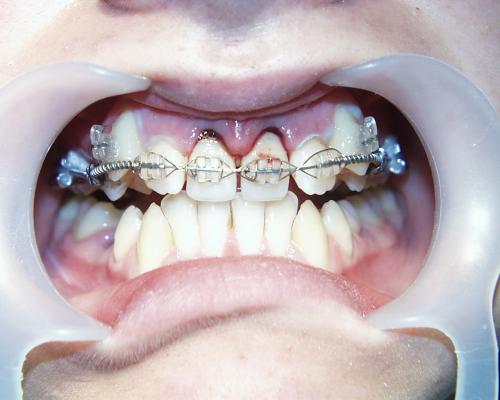

Während der Behandlung

Gleich nach Entfernung der zerstörten mittleren Schneidezähne wurde die feste Zahnspange eingesetzt. Im Bereich der Lücken wurden mit Brackets beklebte Prothesenzähne angebracht. Mit fortschreitender Verkleinerung der Lücke wurde nur noch ein Prothesenzahn belassen (mittleres Bild), der schließlich auch entfernt werden konnte. Die seitlichen Schneidezähne wurden so auf Lücke gestellt, daß sie nach Verbreiterung die Größe von mittleren Schneidezähnen annehmen konnten. Die Eckzähne wurden an Stelle der seitlichen Schneidezähne bewegt (rechtes Bild).